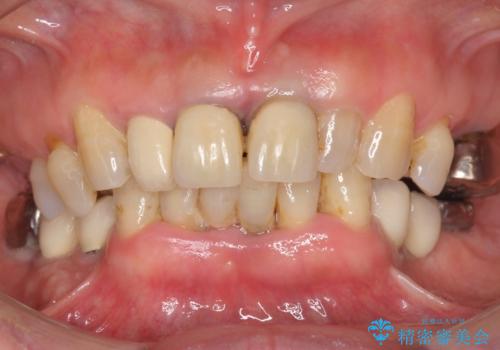

- 上下の前歯が抜けそうだとのことで来院されました。

精査したところ、動揺の著しい上下の前歯は重度の歯周病により保存不可能と判断しました。

ブリッジ、インプラント、義歯の選択肢の中で上下前歯ともにブリッジをご希望されました。